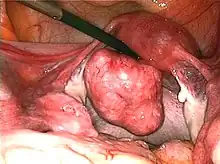

Multiple uterine leiomyoma

Large subserosal fibroid

Multiple uterine leiomyoma with calcification